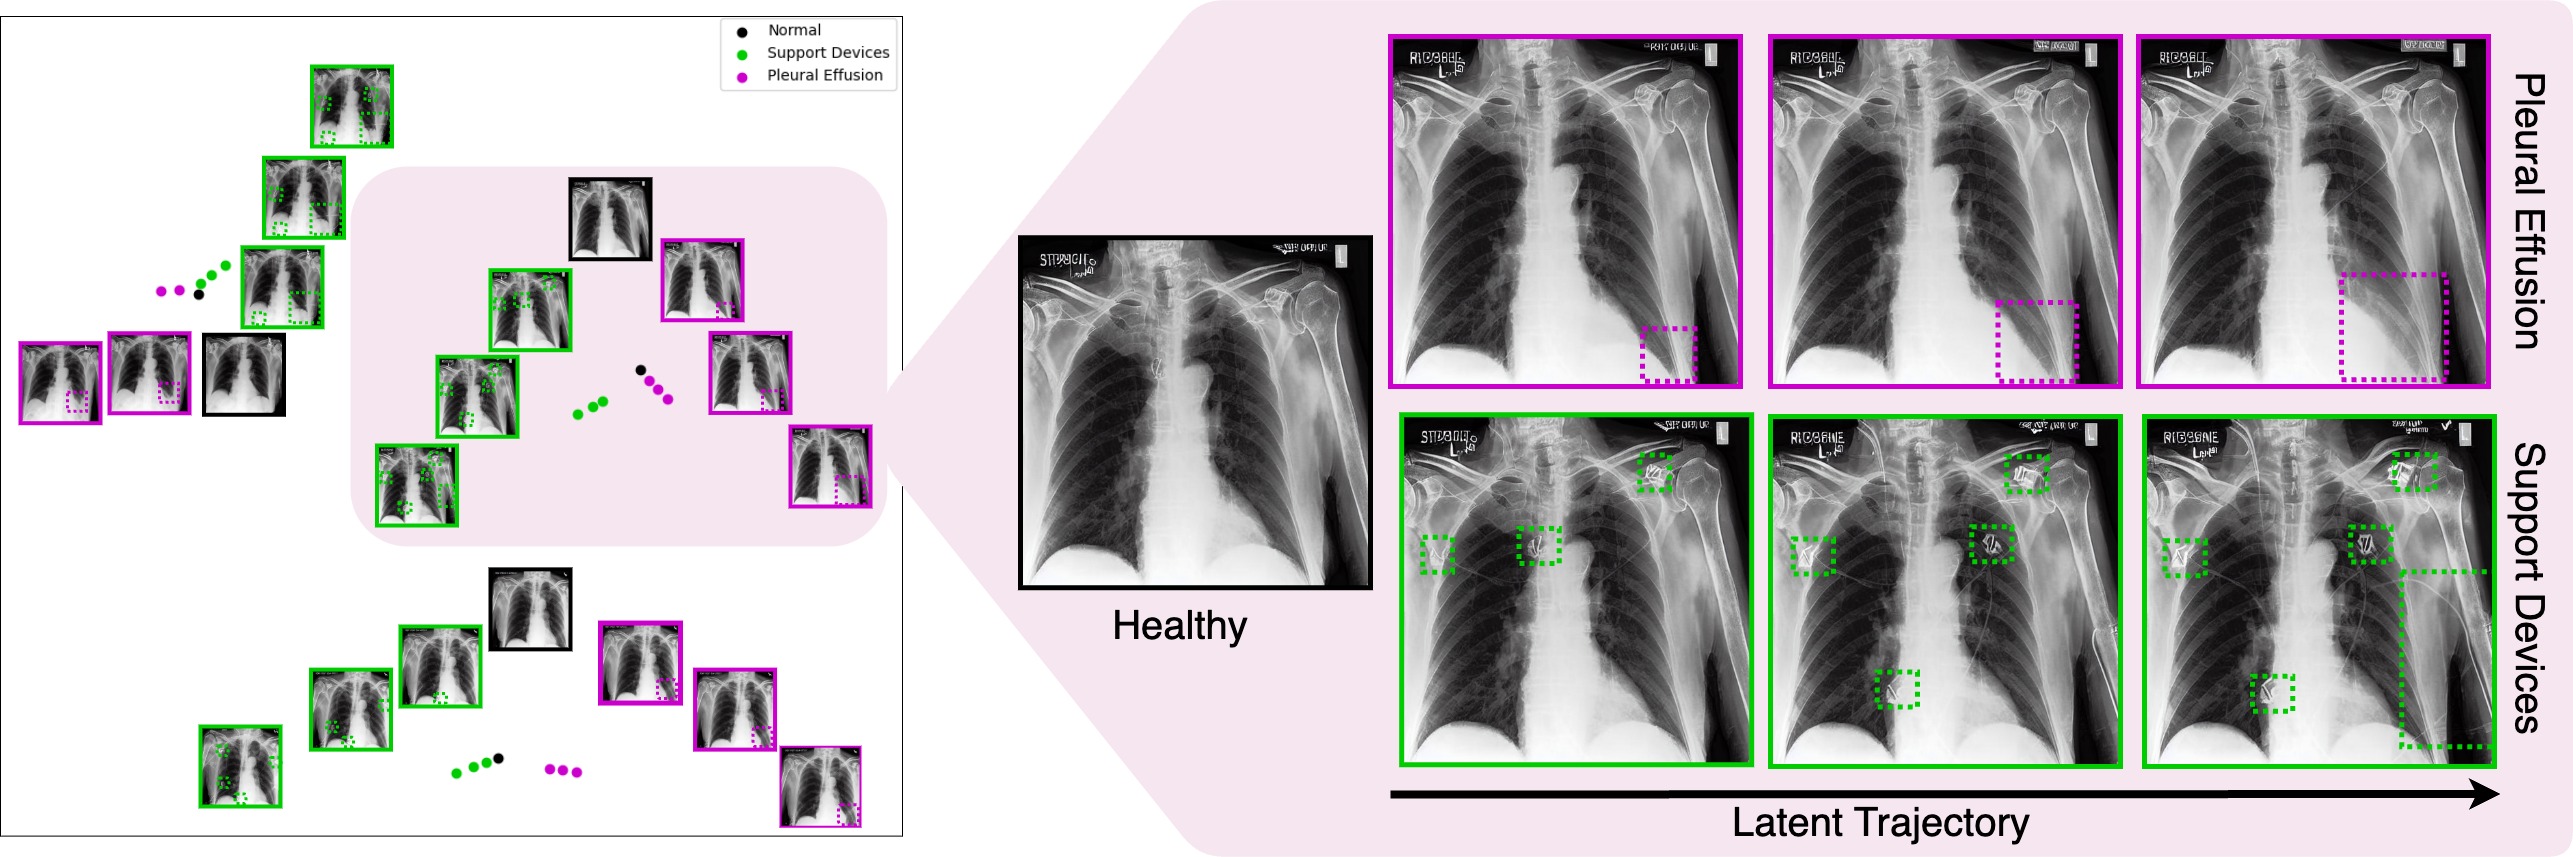

Refer to caption

Figure 1: Traversal along the latent trajectories of Stable Diffusion using language guidance. Given an initial chest X-ray projected onto latent space (start point), traversal along the trajectory is performed via language guidance. Sampling along the trajectory results in only a single attribute (e.g. “medical devices", “pleural effusion") being altered from the start point (“neutral"), while the patient identity is maintained.

Next, we explore the properties of the latent vectors of the conditionally generated images from Stable Diffusion for different attributes. Empirically, for each specific subject, there exist trajectories in the latent space that correspond to specific attributes. The direction along these trajectories can be discovered using an input text prompt. As we traverse in these directions, the desired attribute becomes more prominent in the image without affecting the other confounding attributes, indicating the disentanglement of stable diffusion latent space. This can be seen in Figure 4. To validate our hypothesis further, we also perform a curve fitting through these latent points and sample new points on this interpolated curve. The properties of the images from these interpolated points affirm disentangled trajectories for multiple attributes (shown in Appendix B).